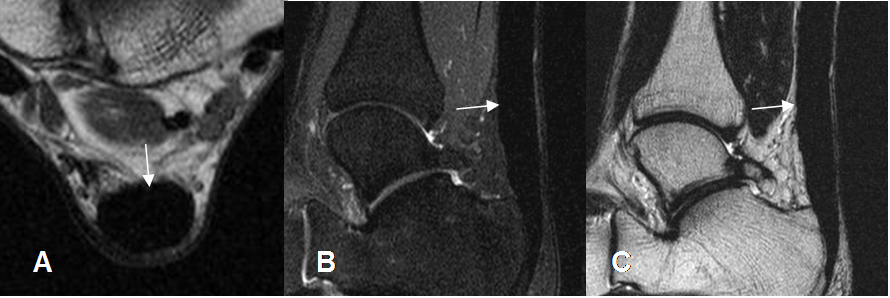

Fig 86. Ruptura insercional del aquiles.

A: RM axial en T2. Area hiperintensa sobre la inserción del aquiles, por ruptura.

B: RM sagital en T2 y C: RM sagital en STIR. Solución de continuidad del tendón a nivel de su inserción, con cambios inflamatorios agudos en los tejidos vecinos.